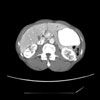

CT scans of the abdomen showed acute infarcts in the medial upper pole and lateral lower pole of the left kidney (Figure). There was no vascular disease in the abdominal aorta, celiac artery, or superior mesenteric arteries. No definite plaque lesions were seen in the right or left renal arteries.

Diagnosis. A CT scan of the abdomen is both sensitive and specific for the diagnosis of renal infarction. With the use of intravenous contrast, renal arteries can also be evaluated for plaques or clots. Sagittal reconstruction through the abdominal aorta can adequately demonstrate findings in the aorta, celiac trunk, and superior mesenteric arteries. Coronal reconstruction of the renal arteries is usually best.